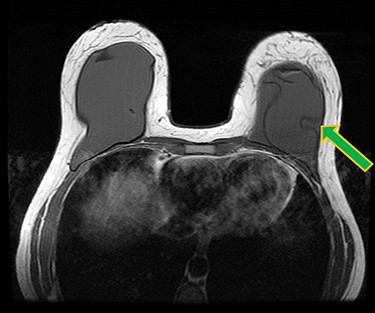

A 42-year-old woman presented for revision of her aesthetic bilateral breast augmentation-mastopexy following multiple implant-related complications. She had initially undergone correction of severe breast asymmetry with mild tuberous breast deformity and Grade-III ptosis in two stages 10 years earlier. Firstly, the breast asymmetry was corrected with a right mastopexy and left breast reduction (Fig. 1A). This was complicated by periareolar fat necrosis on the left and T-junction wound breakdown of the right breast which required debridement and split skin grafting. Subsequently, the second stage was performed comprising differential (inframammary subglandular) breast augmentation with round textured cohesive gel implants (McGhan style 110; left 450 g right 510 g, used prior to the 2018 EU-wide ban). Eight years later however, she represented with significant mastalgia and Baker III capsular contractures bilaterally (Fig. 1B). Having voluntarily lost 50 kg in weight, the patient also noted more prominent ripples in both breasts and an MRI was performed which confirmed a left breast implant rupture (Fig. 2). Bilateral total capsulectomies with implant exchange to anatomical texture silicone implants (Sebbin SM size 590 cc on the right and 525 cc on the left) were performed resulting in satisfactory shape, volume and projection (Fig. 1C). However, she returned 11 months later, complaining of pain associated with her implants and with the position of the implants especially as they dislodged laterally on her lying down (Fig. 1D). On examination, she had good symmetry, soft breasts; however, the implants were hypermobile with a wide intermammary distance and no cleavage (Fig. 1D). Her BMI was 26.4 kg/m2 (after weight loss), her bra cup size a 32F and she was a current smoker (~10 cigarettes per day for 13 years).

Ruptured left breast implant on MRI as demonstrated by the linguine sign (indicated by green arrow).